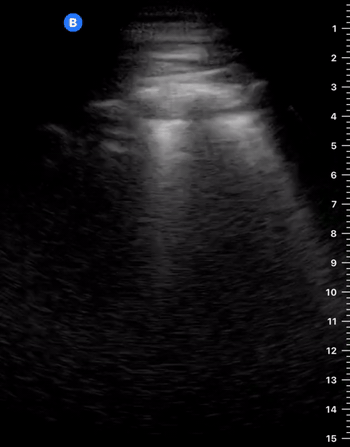

The M mode is far from essential but can be helpful in the interpretation if you struggle to identify sliding in B-Mode. A ‘seashore image’ will be seen in the normal lung, whereas a ‘barcode image’ will appear in absence of lung sliding. Remember, absent lung sliding by itself is not diagnostic of pneumothorax.